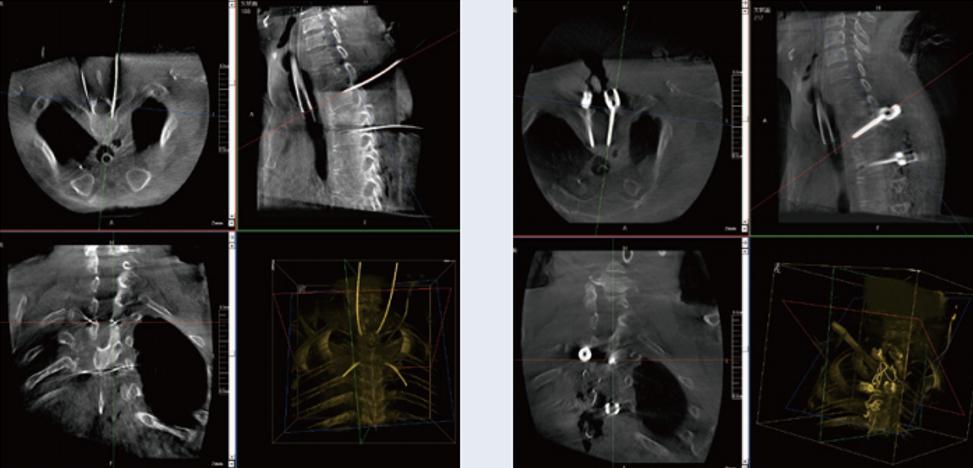

螺釘規(guī)劃后的圖像

植入螺釘后的圖像

術(shù)中三維C臂與骨科導(dǎo)航機(jī)器人配合應(yīng)用,實(shí)現(xiàn)準(zhǔn)確定位,確保了手術(shù)安全、快捷完成。術(shù)后二維、三維影像顯示手術(shù)效果良好,達(dá)到預(yù)期目的。

普愛醫(yī)療三維C臂提供了高質(zhì)量的術(shù)中實(shí)時(shí)三維圖像數(shù)據(jù),保障了骨科導(dǎo)航機(jī)器人手術(shù)的準(zhǔn)確度和安全性,取得不錯(cuò)的手術(shù)效果。同時(shí),三維C臂特有的斷層成像,能幫助醫(yī)生在術(shù)中非常直觀地判斷螺釘植入的準(zhǔn)確度。